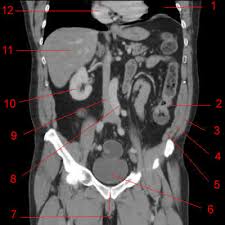

Referiré uno. Una señora, relativamente mayor, presentaba síntomas claros de padecer un cancer de recto; aunque ella se resistía a aceptar su problema, su marido la empujó a venir a la consulta...y se presentó ante mí, estaba tensa, la preocupación se dibujaba en su rostro.

Se completó el estudio, se inició el tratamiento con Radioterapia y Quimioterapia, y se sometió a una intervención quirúrgica, con un resultado favorable: años después está libre de enfermedad.